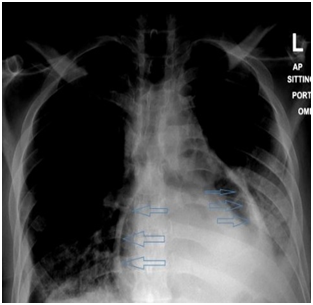

On initial examination, the patient was found to have borderline BP (SBP 101, DBP 60), diminished air entry at the bilateral right and left inferior lung fields. The cardiac examination was remarkable for normal S1, S2 and distended jugular venous distension of 10cm. Chest radiography (CXR) showed an intact esophageal stent along with radiolucent rim surrounding the cardiac silhouette (Figure 1). Echocardiogram (echo) revealed an air gap sign echoic dense space at the anterior and basal part of the heart consistent with the pneumopericardium with no signs of tamponade (Figure 2).  Computed tomography (CT) scan chest confirmed the presence of pneumopericardium in anterior pericardium along with left sided mediastinal pocket of air with foci of gas above the esophageal stent likely communicating with the pericardium (Figure 3). Given the clinical and radiological evidence of the symptomatic large pneumopericardium, we consented the patient on an emergency pericardiocentesis. Goals of care were discussed with the patient and his family and the patient opted interventional care measures. A following pericardiocentesis (with off label CT guidance) right sided parasternal approach (marked at the right 5th intercostal space with angulated entry projection of 70 degree medially with 27mm depth) was performed successfully with aspiration of 70ml of air followed with frothy blood-stained aspirate. The gentleman symptoms resolved immediately with picked up BP (SBP 123,DBP 67) and pigtail kept and secured in place for 5days without any complications.  Thereafter, a follow up echo and CT scan repeated and showed bright improvement in the clinical status (Figures 4 & 5) respectively.

Figure 1 (Sitting CXR showed radiolucent rim surrounding the cardiac silhouette).

Figure 2 2Dimension -4 Chamber apical view- showed air swirling (blue arrows) along with pericardial effusion (PE) in the pericardial cavity.